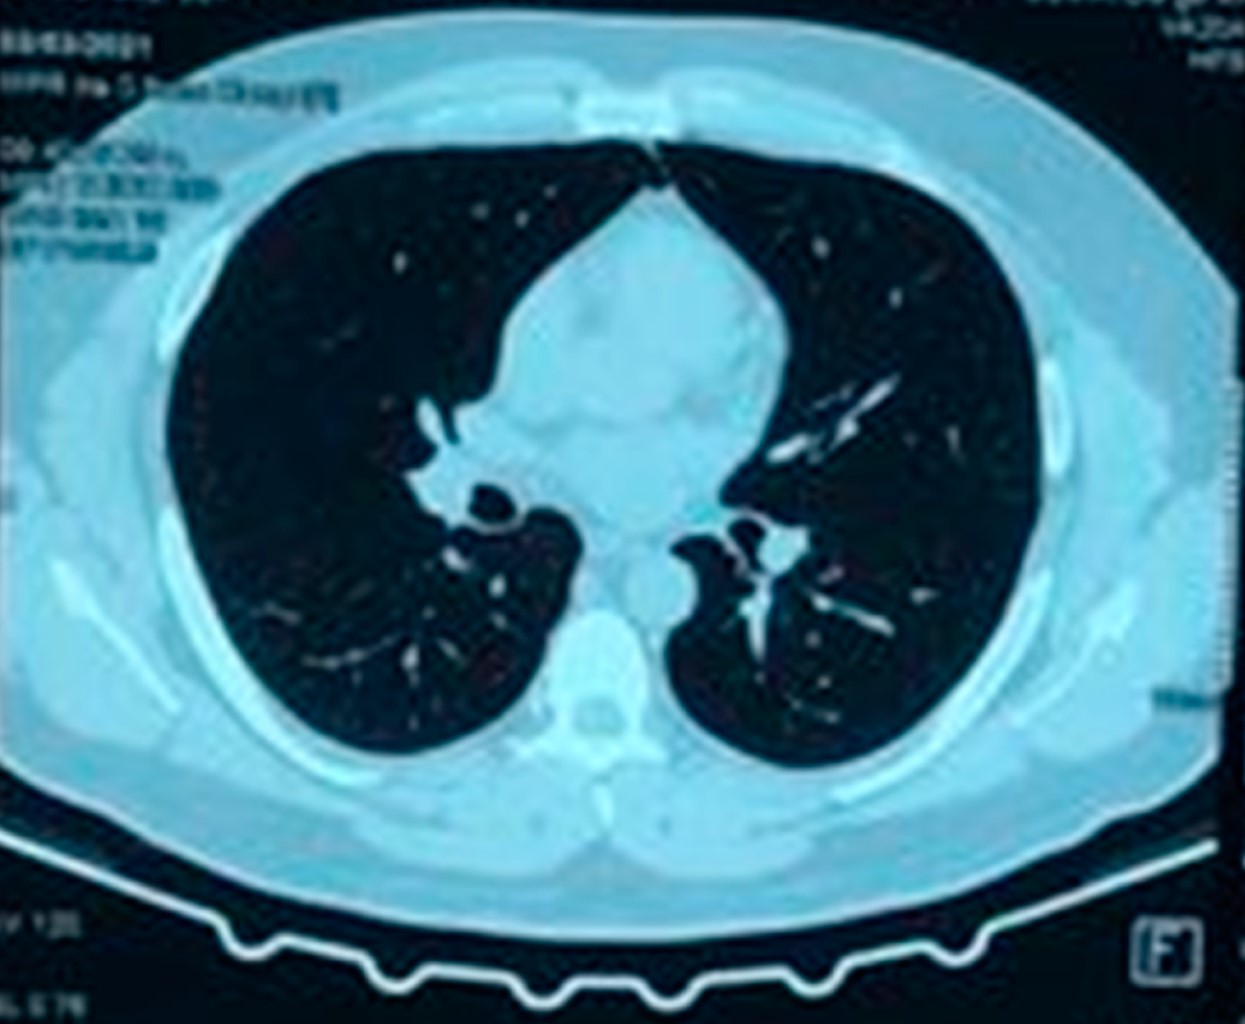

Masculino de 38 años de edad destaca dedicación a la ganadería caprina, sin uso adecuado de equipo de protección personal. Acudió al servicio de urgencias por cuadro clínico de un mes de evolución con presencia de fiebre de predominio nocturno de 39 oC, duración de tres horas, astenia, adinamia, con signos vitales tensión arterial:130/80 mmHg, frecuencia cardiaca:100 lpm, frecuencia respiratoria: 20 rpm, temperatura: 37 oC. A la exploración física sin existencia de adenopatías palpables, sin alteraciones pulmonares ni cardiacas, abdomen sin alteraciones. En la analítica hemoglobina: 17 g/dL, plaquetas: 362 × 109/L, leucocitos: 14.8 × 109/L, neutrófilos: 10.3 × 109/L, PCR SARS-CoV-2 negativa, examen general de orina y urocultivo negativos, IgG Coxiella fase I negativo, IgG Coxiella fase II positivo, IgM fase I Coxiella positivo 1,256 U/mL, IgM fase II Coxiella positivo 116,384 U/ml, radiografía simple de tórax (Figura 1), tomografía simple de tórax (Figura 2). Ecocardiograma transtorácico (Figura 3). Se inició tratamiento con paracetamol 1 gramo intravenoso cada ocho horas y doxiciclina 100 mg vía oral cada 12 horas durante dos semanas (14 días) con mejoría.

Figura 3